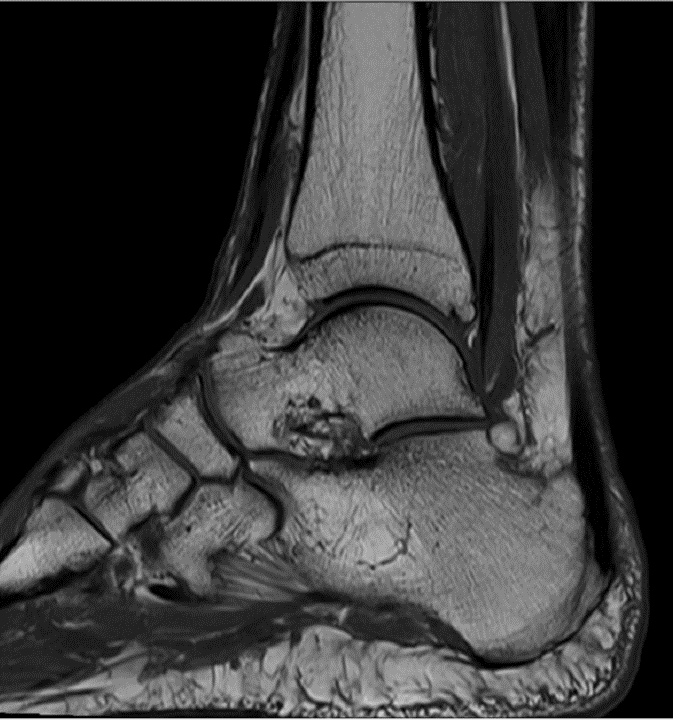

MRT-Bild meines Fußes